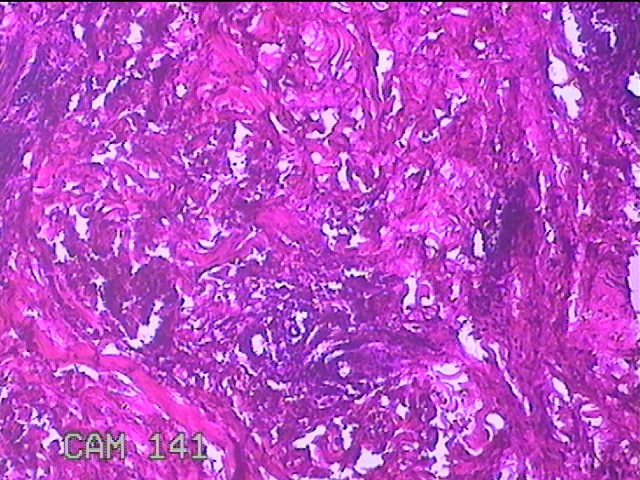

性别

女

年龄

39岁

临床诊断

皮下结节

一般病史

发现左臀部多发性结节5年余。

标本名称

左臀部结节

大体所见

灰白粉红色结节0.7x0.3x0.2cm一个,表面糜烂。

图4